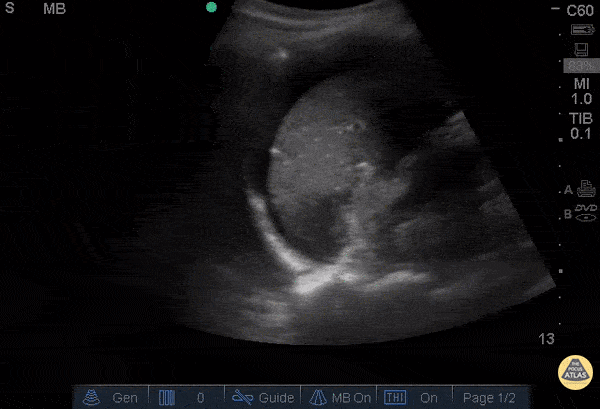

View: Unspecified Parasternal Long Axis Parasternal Short Axis Apical Four-Chamber Subcostal Four-Chamber Subcostal Inferior Vena Cava Right Upper Quadrant Left Upper Quadrant Suprapubic Longitudinal Suprapubic Transverse Subxiphoid Anterior Thoracic Phrenic